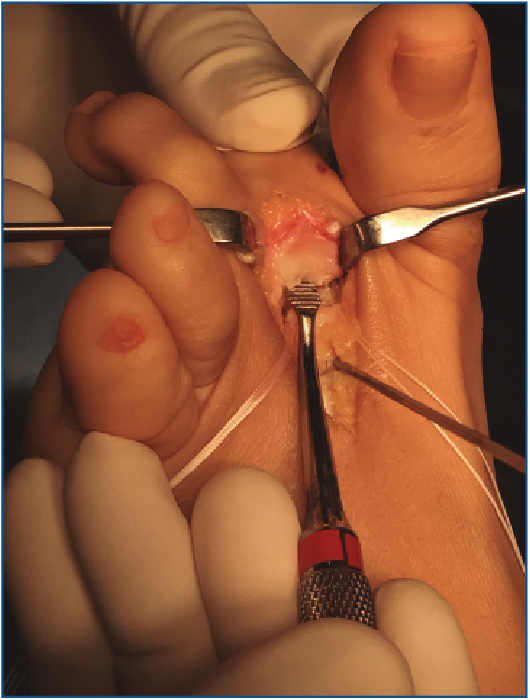

5. Pasamos las suturas por la placa plantar con ayuda de una pinza Mini-Scorpion DX® (Arthrex) (Figura 7) o de un Micro SutureLasso® (Arthrex) (Figura 8). Existen diferentes técnicas según el tipo de rotura. Para la reinserción utilizamos 2 suturas no reabsorbibles de Fiber-Wire® n.º 0 en “doble hilera” proximal y distal (Figura 9). Decidimos una u otra configuración in situ según el tipo de rotura.

Figura 7. Pase de suturas mediante pinza Mini-Scorpion®.

Figura 8. Pase de suturas con ayuda de Micro SutureLasso®.

Figura 9. Disposición de las suturas con técnica de “doble hilera”.